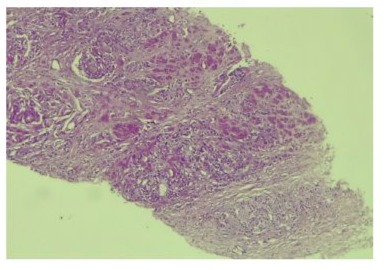

This was a 69-year-old patient who had been admitted at the surgical emergency department for painful abdominal distension associated with constipation and absence of flatus evolving for 3 days before his admission. The medical observation revealed symptoms evolving for more than a year consisting of alternating episode of diarrhea and constipation, 2 episodes of proctorrhagia 3 and 2 months ago. which were associated with significant weight loss (> 10% of body weight), asthenia and anorexia. However, the patient did not report any lower urinary tract symptoms. The physical examination noted a poor general condition (ECOG Performance Status Scale Grade 3), a distension of the abdomen, tender and increase percussion node, a large stony mass with an irregular surface, painless, filling the entire rectal lumen, with the absence of stool on the examination finger. The rest of the physical examination revealed no other abnormalities. The abdomino-pelvic CT performed (Figure 1).

Figure 1: Abdominal-pelvic CT sagittal section showing a low colonic occlusion of mechanical origin

concluded that there was a complete mechanical digestive obstruction by a tumor occupying the entire lumen of the middle rectum with extension to the prostate. The diagnostic hypotheses mentioned were: locally advanced obstructive rectal cancer or prostate cancer with invasion of the rectum. The initial diagnosis was that of an obstructive rectal tumor on preliminary clinical-radiological data. An emergency bowel bypass by a bi-tubular colostomy with biopsy of the rectal mass was performed to diagnostic confirmation. The histopathological examination of the biopsy fragment concluded that adenocarcinoma of the prostate was Gleason 9 (4+5): ISUP 5. (Figure 2).